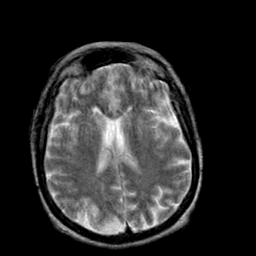

Creutzfeld-Jakob disease: T2-weighted MR -- Slice #14

[Home][Help][Clinical] Slice 14